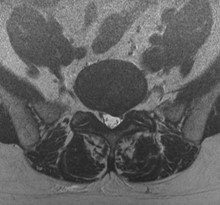

検査

当院では、術前の診断精度を高める目的で、神経根ブロック(左)やCTミエログラフィー(右)検査を行っています。検査後は、経過を確認する目的で1泊入院となりますが、翌日には退院が可能です。